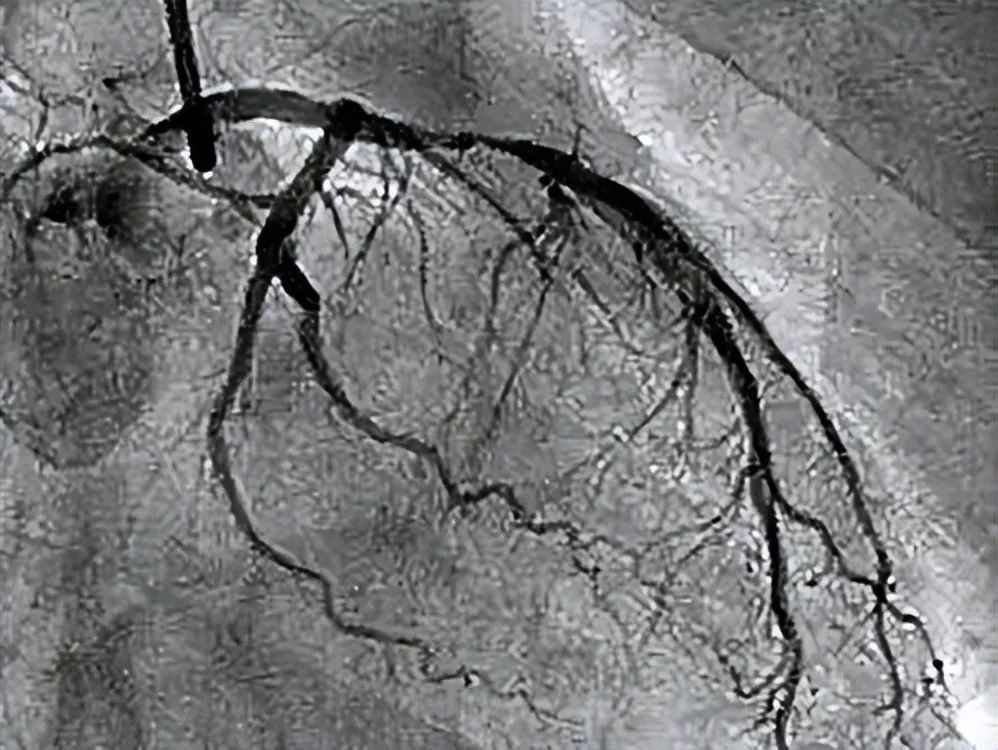

谣言1:支架是淘汰的技术,国外早就不用了?

很多人在网上整天说,支架都是人家欧美淘汰的技术,人家早就不用了,才卖给咱们的。其实目前对于严重的心血管狭窄和急性心肌梗死,支架仍是最前沿的方法,即使在欧美日本等发达国家,目前支架技术仍是最主要的治疗手段。

谣言:9:心血管狭窄都必须支架

当心血管狭窄超过50%的时候,都叫冠心病。但只有心血管狭窄超过75%且有足够的心肌缺血的证据,才需要支架治疗。中度轻度的心血管狭窄通过健康生活和正规药物就能控制。